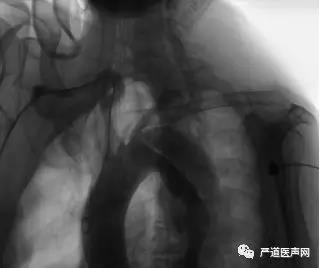

患者1天前已行弓上分流术。全麻气管插管。穿刺右侧肱动脉,TIG造影导管至左、右冠脉口行冠脉造影。

造影结果示:LM、LCX未见明显狭窄,LAD中度80%狭窄,RCA中段70%狭窄,前向血流TIMI3级。

接下来,送猪尾导管至升主动脉行主动脉造影。

TEVAR+ IA chimney术前主动脉造影

造影结果示:主动脉弓上分流血管血流通畅,患者为主动脉夹层(Stanford B型、DeBakey III型),破口位于主动脉弓-左锁骨下动脉开口以远处并逆撕至左锁骨下动脉开口前缘。结合术前主动脉CTA诊断结果,决定行胸主动脉腔内隔绝术+头臂干烟囱支架植入术。